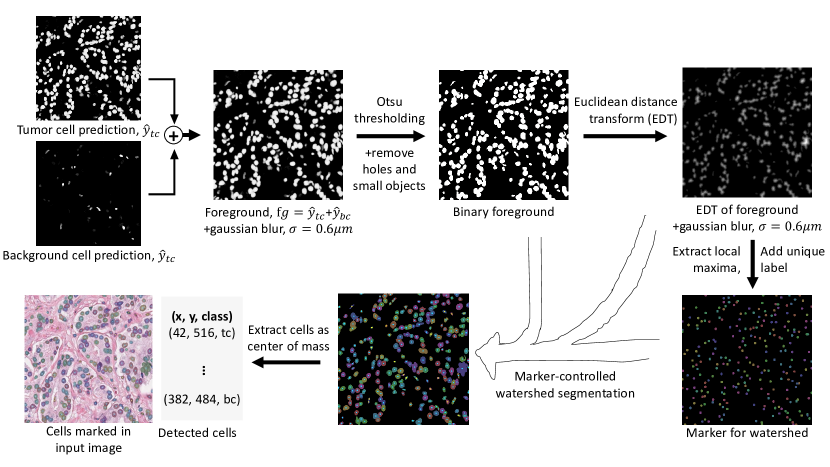

Appendix 0.B Postprocessing for the hard IS ground truth format

For the hard IS ground truth format, cell detection candidates are extracted by first combining the tumor and background cell prediction into a foreground prediction. The Otsu threshold is then applied on the foreground, resulting in a binary foreground map, from which holes and small objects are removed using the skimage.morphology.remove_small_objects and scipy.ndimage.binary_fill_holes functions. Next, we calculate the Euclidean Distance Transform (EDT) on the binary image, revealing the distance of each pixel to the nearest background pixel and, consequently, highlighting potential cell instances as peaks. To identify these peaks, we employ skimage.feature.peak_local_max function, assigning each peak a unique identifier. These identified points serve as markers in a marker-controlled watershed technique, facilitating the separation of connected objects within the binary foreground map. The inverse EDT (-EDT) is used as a cell border indicator. The final cell candidates are determined by locating the center of mass within each segmented instance of the watershed segmentation. The cell class is assigned as the class with the majority of class pixels in each cell instance.